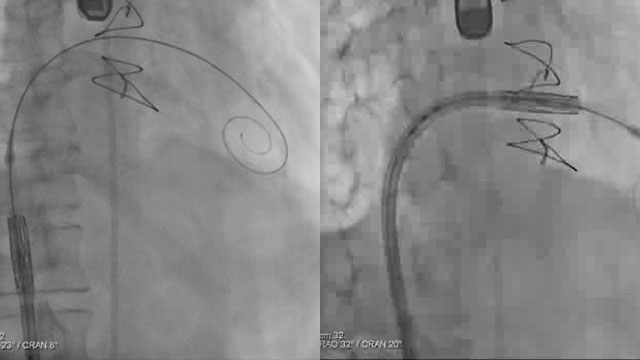

A challenging valve-in-valve scenario in a patient with prior aortic coarctation repair

16 Feb 2026

A 79-year-old with a degenerated aortic bioprosthesis after complex coarctation surgery challenges conventional strategies. Which access route would you choose?